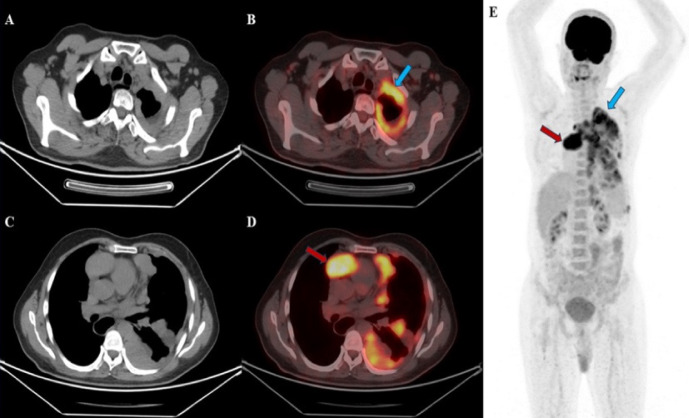

The majority of metastatic pleural lesions are caused by malignancies such as bronchogenic carcinoma (40%), breast cancer (20%), lymphoma (10%), and ovarian or gastric carcinomas (5%). However, pleural metastases from thymoma are extremely rare. In this report, we present the 18F-fluorodeoxyglucose (18F-FDG) positron emission tomography/computed tomography (PET/CT) imaging findings of a patient with thymoma and extensive pleural metastases. Although biopsy remains the gold standard for diagnosis, it is important to consider high grade thymoma in the differential diagnosis, as extensive pleural involvement observed on 18F-FDG PET/CT imaging can mimic both primary and metastatic pleural malignancies. Recognizing this possibility can assist in more accurate interpretation of imaging findings.